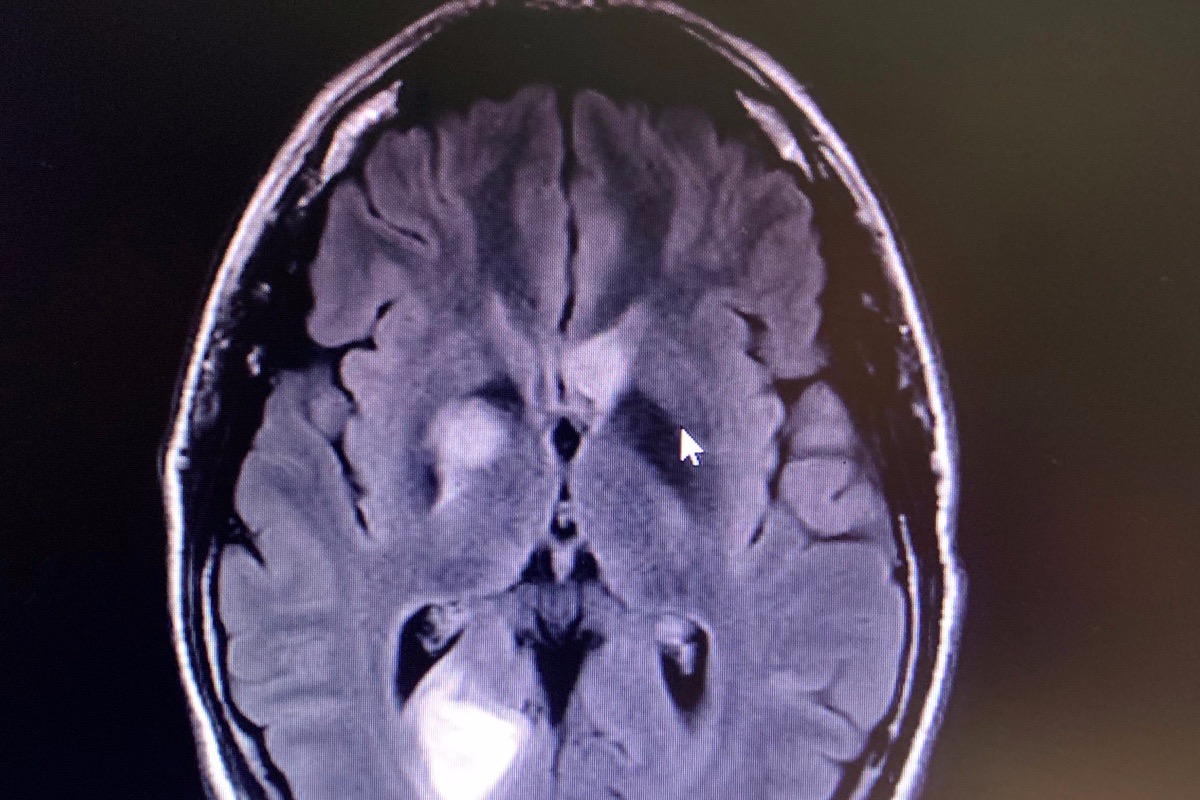

In July 2018 Anthony found out he had the deadliest form of skin cancer, Stage 3c Melanoma. After surgeries he was NED (no evidence of disease). With what he thought was behind him he began to rebuild and love life to a greater degree. Unfortunately, one year later the cancer has returned to his BRAIN!! He has over 20 tumors. The one that impacted his eye sight is seen in this scan.

From that appointment on Friday he was sent to the University of Michigan hospital for an MRI. At 3 o’clock in the morning the doctor walked in to inform us that he had over 20 brain tumors and that they would be admitting him. It was such a devastating blow to both of us to learn. While in the hospital it was determined that the cancer had also spread into areas near his lungs. The beast came back fast and furious.